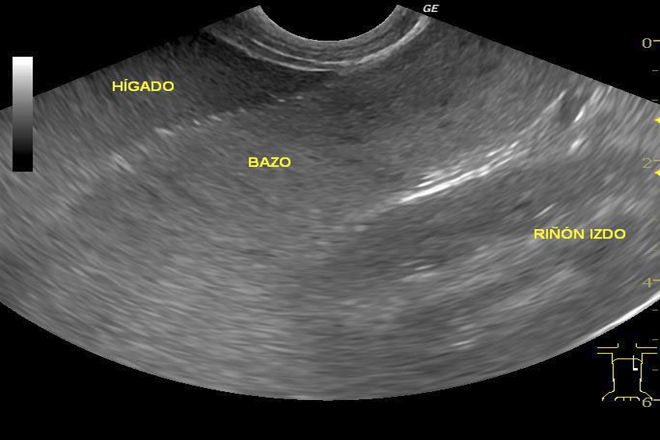

En pacientes con infecciones recurrentes, las mediciones del bazo y del timo por ultrasonido son clave para evaluar la respuesta inmune. Dichas mediciones se vuelven especialmente significativas entre los 12 y 23 meses de vida. El tamaño del bazo, expresado mediante el índice esplénico, disminuye en comparación con la depleción tímica, que se mide a través del índice tímico en pacientes con rastreo mediastinal y abdominal.

La medición más estandarizada del bazo es la longitud en vista coronal, que incluye el hilio. Por otro lado, el índice tímico se calcula en la sección longitudinal de ambos lóbulos del timo entre la 2da y la 4ta costilla a nivel del esternón.

1. Bazo:

Dimensiones aproximadas:

• Longitud: 12cm

• Eje antero-posterior: 7cm

• Espesor: 3-4cm

• Peso promedio: 150g (rango: 80-300g)

Se pueden observar diferentes condiciones como esplenomegalia, quistes, metástasis y eventos como infarto esplénico, sarcoidosis, hemangioma y tuberculosis.